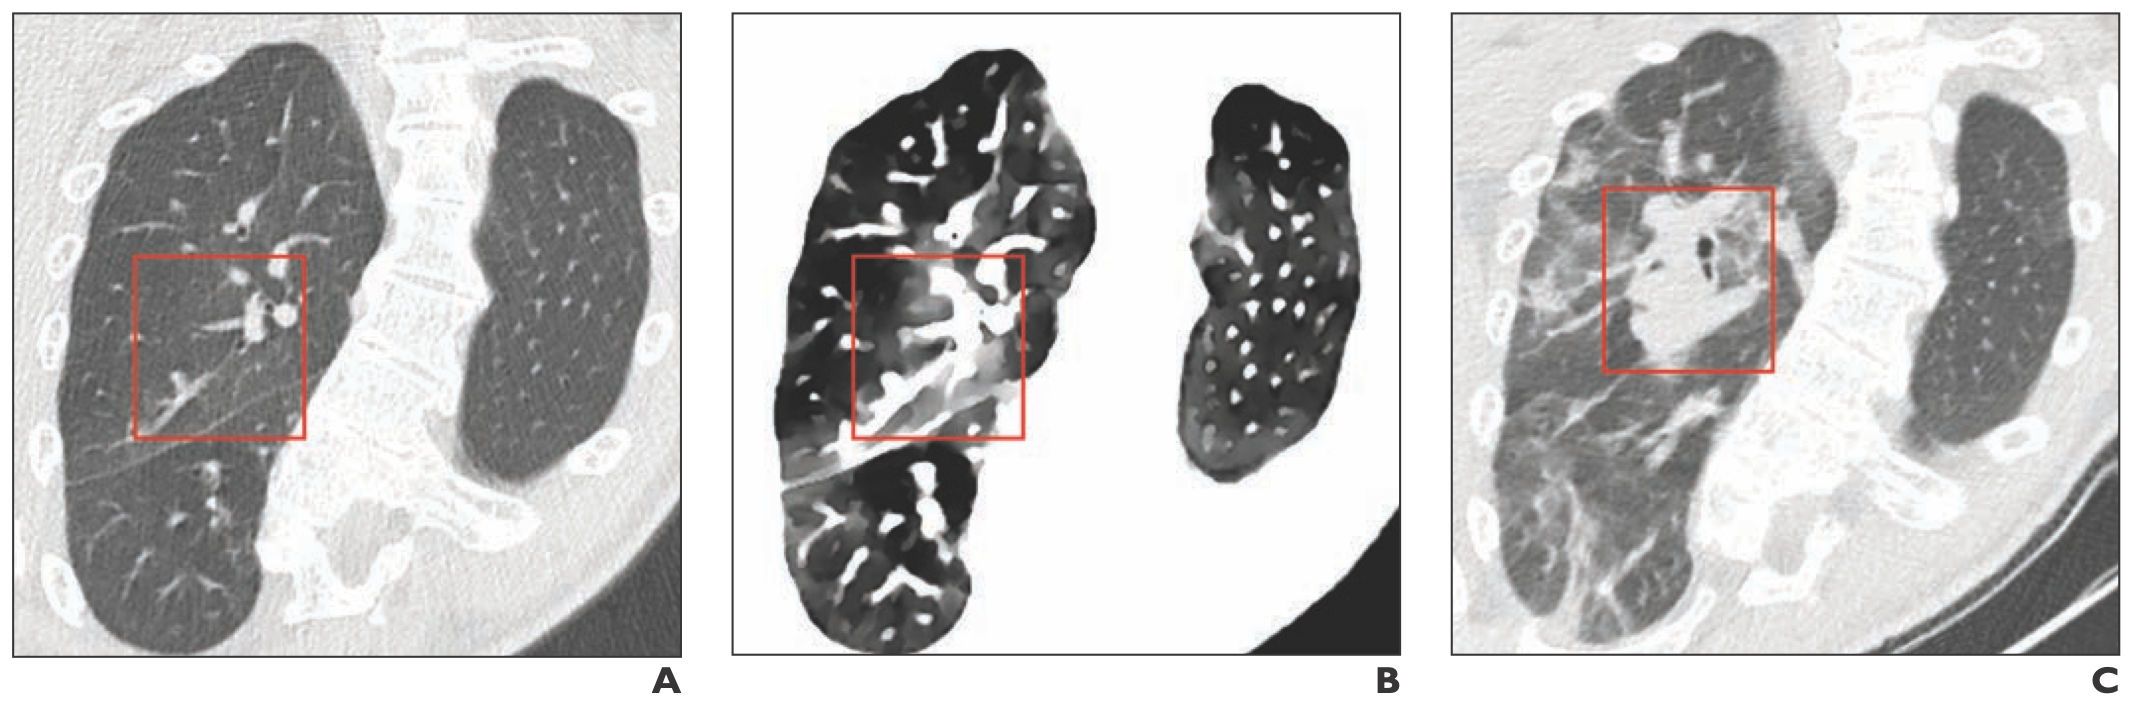

Chest MRI picks up the same characteristics of COVID-19 pneumonia that are seen on chest CT, making it a good alternative without the radiation.